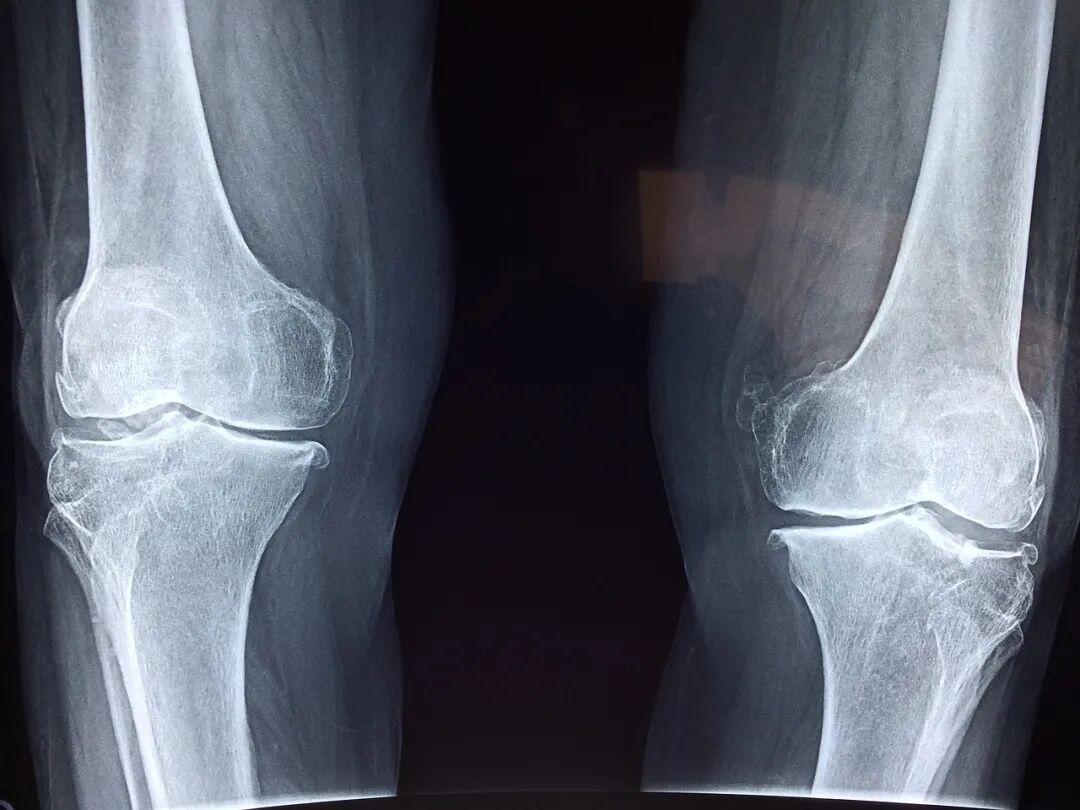

图片

图片来源于网络